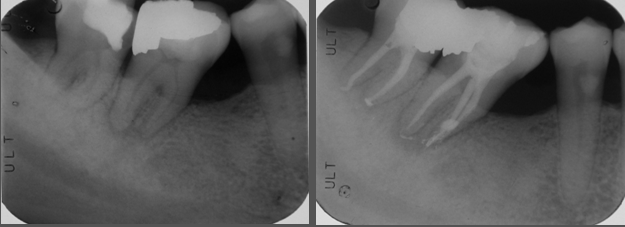

術前、術後比較

患者的症狀改善理想